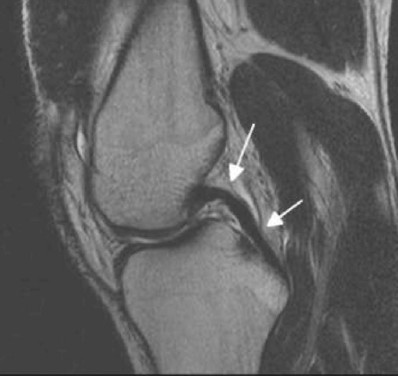

Разрыв передней крестообразной связки на МРТ снимках

МРТ коленного суставаБлагодаря МРТ  специалисты диагностируют три степени разрыва данной связки: микро-, частичный и полный разрыв. При первом случае целостность связки нарушена только на небольшом участке, во втором происходит повреждение до половину волокон, в последнем – полностью утрачивается целостность связки и конечность перестает выполнять опорную функцию.

В зависимости от степени разрыва МР-картина может содержать разные сведения о состоянии связки, например, снижается толщина суставного гиалинового хряща, сама передняя крестообразная связка может быть истончена, разволокнена и представлена тонкой струной, что говорит о частичном разрыве.

При частичном или полном разрыве в заключении рентгенолог рекомендует консультацию ортопеда, а также указывает на целесообразность оперативной реконструкции связки из-за малосостоятельной функциональной пригодности данной структуры.